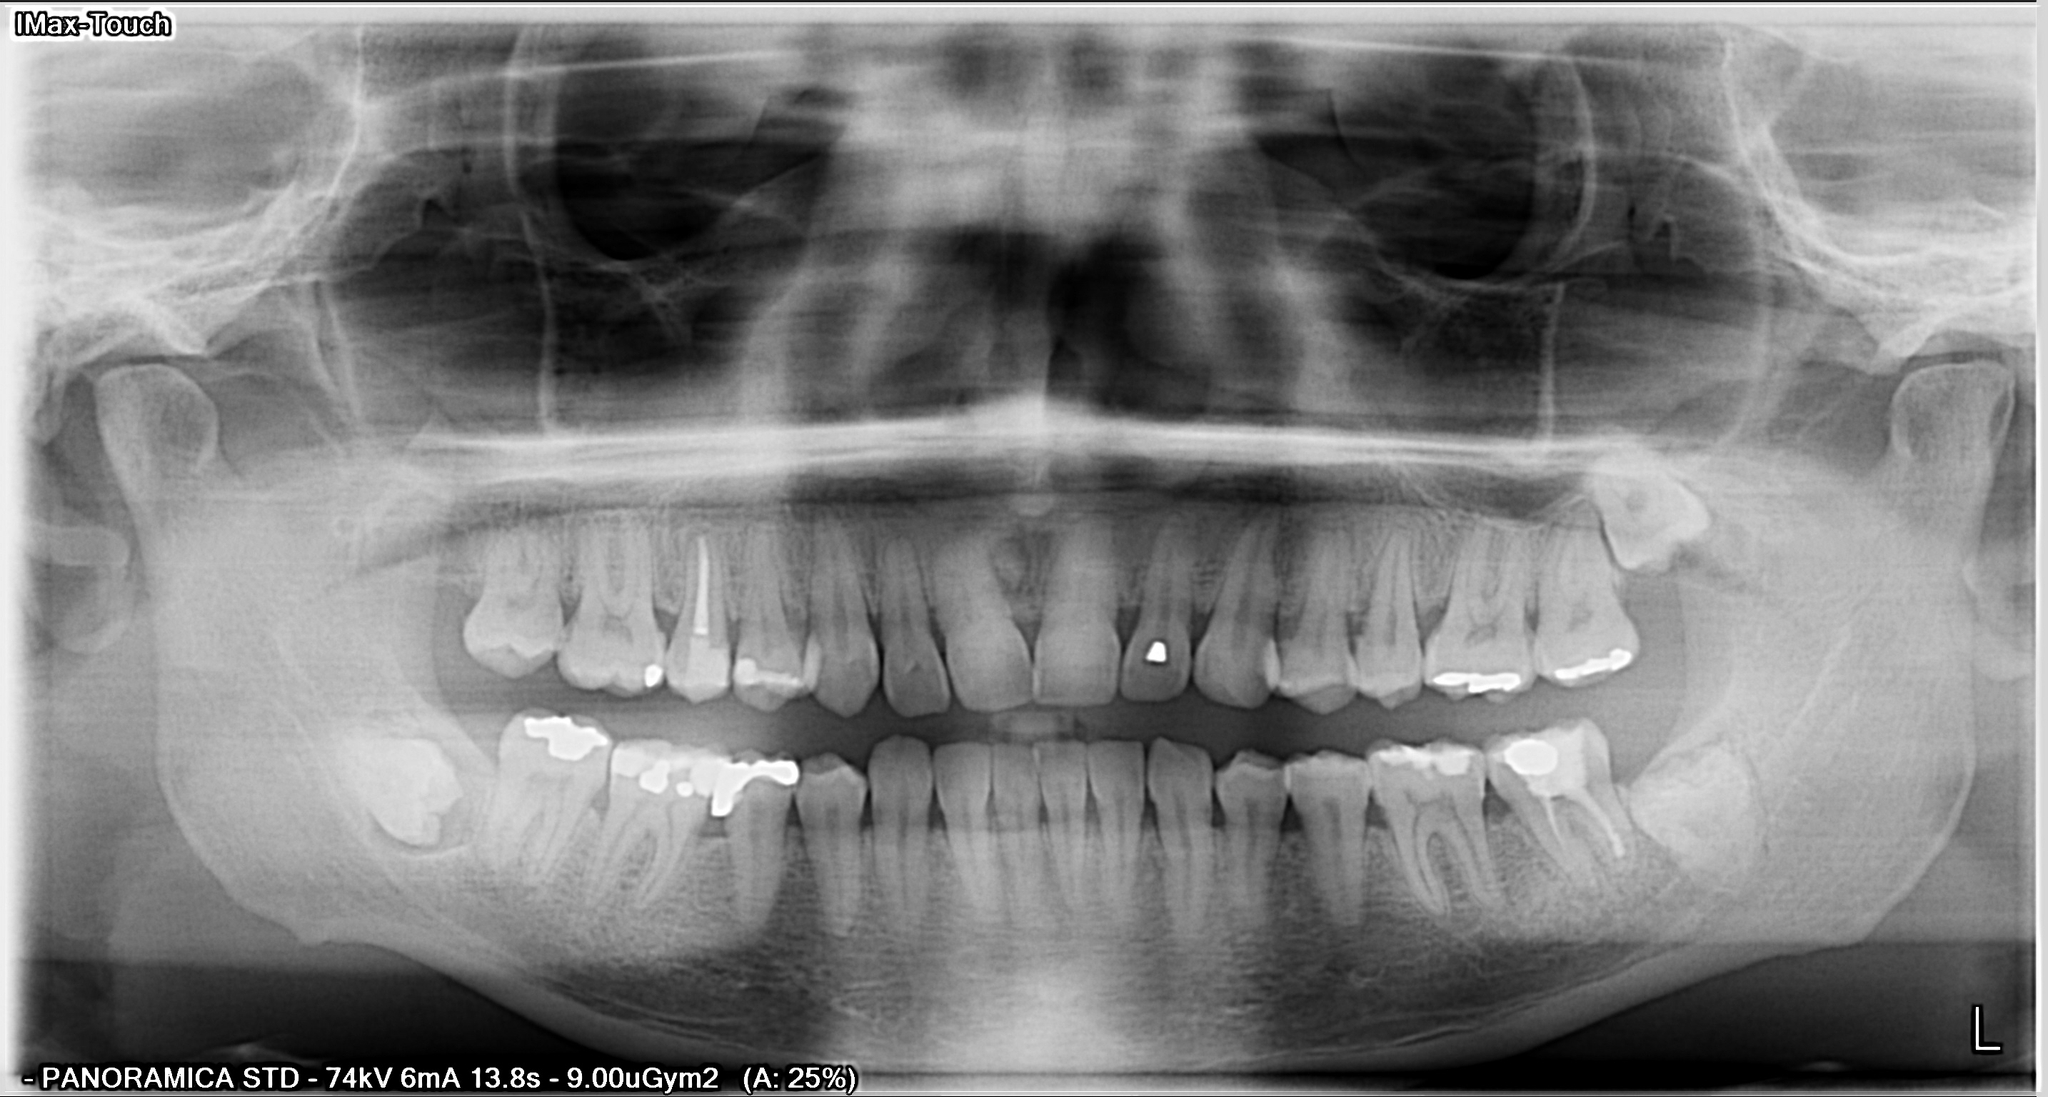

Lo Studio è dotato di un moderno sistema di radiologia digitale NewTom 3D TC di ultima generazione Cone Beam che in soli 15/20 minuti esegue un completo esame tridimensionale. Progettato dai pionieri del CBCT 3D in ambito dento-maxillofacciale, NewTom offre le migliori performance e la straordinaria qualità dell’imaging 3D. Direttamente nel vostro studio di fiducia, è possibile eseguire esami radiografici completi del complesso maxillofacciale con tecnologia UHD digital di ultima generazione a ridotta emissione di radiazioni per esposizione.

Sezioni Tomografiche (TC/Tac) e Ricostruzioni 3D dei mascellari Ortopantomografia delle arcate dentarie a bassa emissione di radiazioni X Ortopantomografia delle arcate specifica per uso pediatrico Rx Stratigrafia dei condili mandibolari compresa ATM Emimandibola dx/sx Adatta per adulti e bambini, veloce e indolore, consente di ottenere in tempo reale i referti necessari per le diagnosi e la pianificazione delle cure. Lo specialista garantisce le stesse tariffe applicate presso le strutture sanitarie specializzate esterne pur offrendo un prodotto avanzato, confortevole e sicuro.